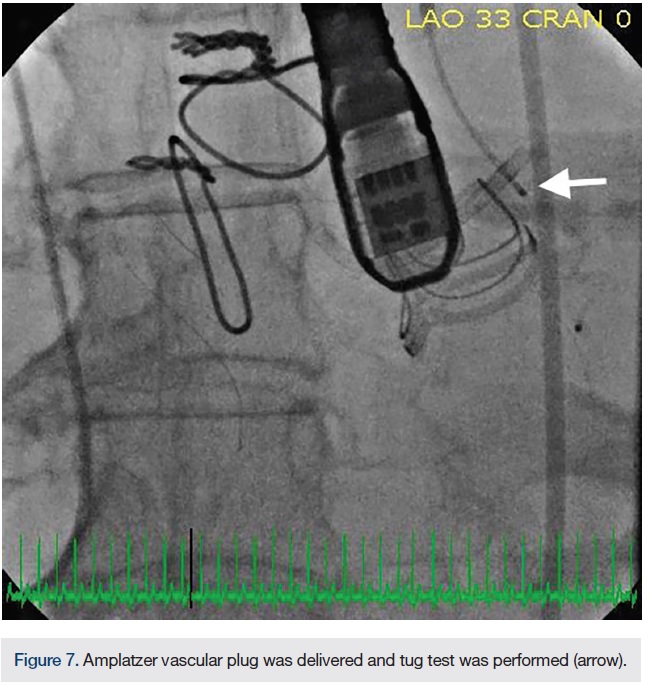

At this point, the approach was changed. The Extra Back-Up (EBU) 3.5 guide was advanced from the femoral approach to selectively engage the left main ostium. The EBU guide was left in place to protect the left main ostia, because the paravalvular leak was closed to the left main origin. Using a 5 French JR4 guide catheter via the right radial access, we were able to successfully advance the JR4 guide catheter through the paravalvular leak (Figure 5). A 5 French, 90cm Destination sheath was telescoped over the 5 French guide catheter across the PVL. Under TEE and fluoroscopic guidance, an 8mm Amplatzer Vascular Plug (St. Jude Medical) was deployed across the PVL and through the Destination sheath, and a tug test was performed. (Figure 6A-B, 7). The final TEE imaging showed a well-deployed Amplatzer Vascular Plug into the paravalvular aortic annular defect, with a significant decrease in paravalvular regurgitation compared with the pre-procedure study (Figures 8, 9). A trace to mild paravalvular insufficiency and a mild intrinsic central aortic insufficiency were seen (Figure 10). A hemostatic band and a vascular closure device were used to achieve hemostasis in the radial artery and femoral artery, respectively. The patient tolerated the procedure well and she was discharged from the hospital the next morning. At her follow-up visit, she had significant improvement in her symptoms.